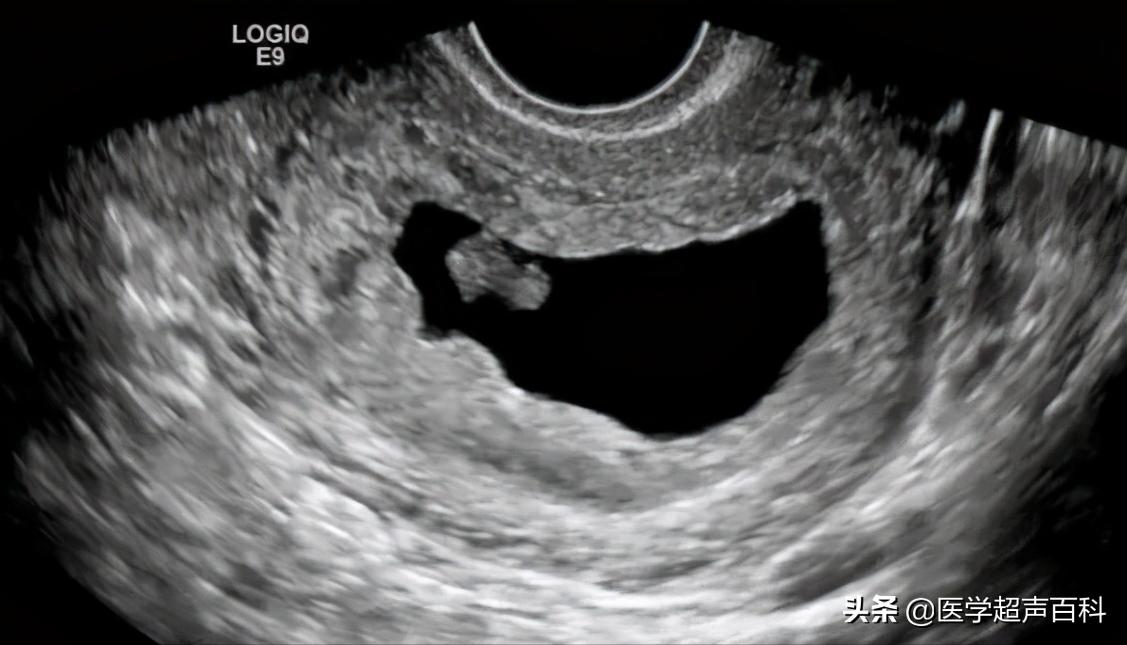

2、有胚芽无胎心B超示妊娠囊内可见胚芽,但无胎心搏动。

3、有胎心后停育是指B超在动态监测妊娠囊,可以先有胎芽胎心搏动,待一段时间 B超又未监测到胎心搏动,只见枯萎的妊娠囊。

1、胚胎长度≤5mm,无心管搏动,7-10天后复查仍无心管搏动。

2、胚胎长度>5mm,无心管搏动或妊娠囊平均内径>20mm,无卵黄囊及胚胎。

3、妊娠囊平均内径≤20mm,无卵黄囊及胚胎,1-2周后复查仍无卵黄囊及胚胎。